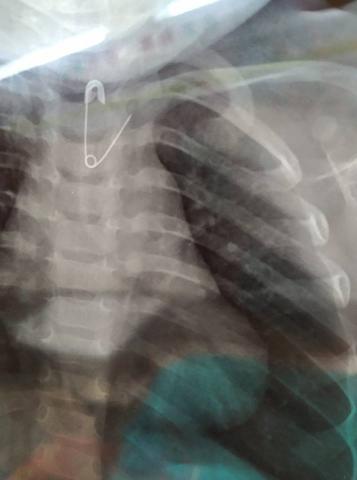

-Μεγάλα αιχμηρά αντικείμενα (καρφίτσες – παραμάνες – οδοντογλυφίδες) ελλοχεύουν κίνδυνο διάτρησης και συστήνεται να αφαιρούνται. Μικρότερα αιχμηρά αντικείμενα (πχ πινέζες) μπορεί προωθούνται στο πεπτικό αλλά χρήζουν παρακολούθησης (έως και 15 ημέρες) ώστε εάν ενσφηνωθούν για >72 ώρες ή επί ανάπτυξης κλινικών συμπτωμάτων επιπλοκών, να ακολουθηθεί ενδοσκοπική ή χειρουργική αφαίρεση (ανάλογα με την θέση τους).